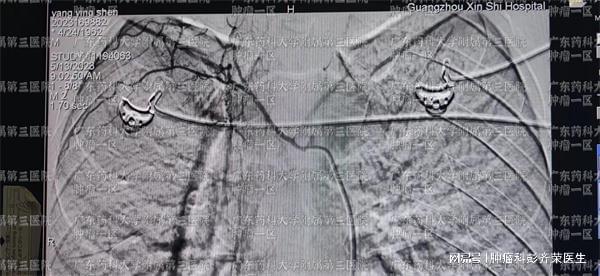

对食道肿瘤,广东药科大学广州复星禅诚医院肿瘤一区医生表示,还是有很多其他的治疗方法可以选择的。随着科学进步,越来越多的医学技术也应用到了肿瘤治疗领域。对食道肿瘤,包括已转移或未转移的晚期患者,肿瘤科一区可以为患者提供动脉灌注栓塞治疗、粒子植入、氩氦刀治疗、微波消融、富血小板抗肿瘤治疗、靶向治疗、免疫治疗、中医治疗等等多种治疗技术。

彭齐荣教授表示,中晚期食道肿瘤患者,由于癌细胞发生了游离,且局部病情严重,对癌症患者的治疗需要多点齐下,综合治疗。彭齐荣教授表示,对身体状态较好的患者,可以根据食道肿瘤病理类型,调配好治疗药物后,利用动脉灌注栓塞治疗或氩氦刀等局部微创治疗技术,进行病灶的局部治疗。同时在微创术后,利用免疫治疗或中医治疗或富血小板抗肿瘤治疗等全身技术,进行巩固治疗,增强微创治疗疗效的同时,加强患者抵抗力,消灭游离的癌细胞,降低复发转移的风险。